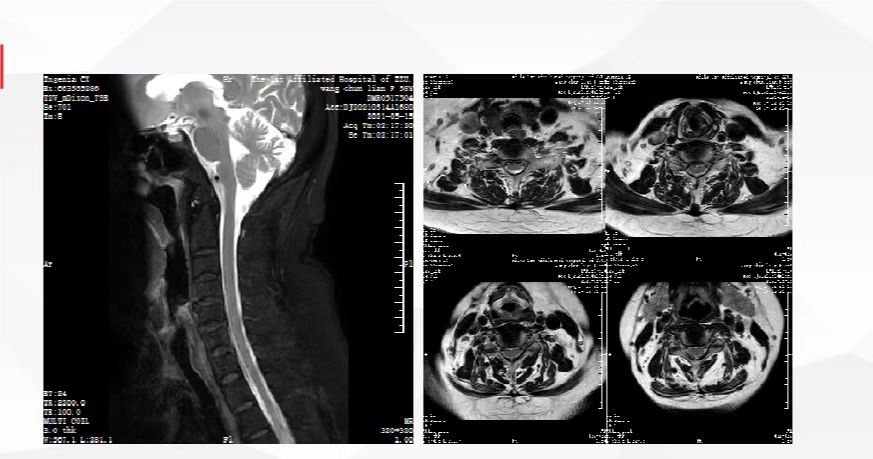

根据患者的发病特点,我们给出入院诊断:一、肩周炎?二、肩袖损伤?三、2型糖尿病。当然,我们还要与可能引起肩关节疼痛的其他疾病相鉴别,如肩关节肿瘤、肩关节感染、颈椎病、冠心病、肺或胸膜病变。 患者入院后,我们为患者安排相关的医学检查,以明确诊断。肩关节感染和肿瘤可以引起肩关节疼痛和活动受限。患者的血常规检查、肝功能检查、肾功能检查、肿瘤标志物筛查结果都是正常的,空腹血糖17毫摩尔/升,糖化血红蛋白9.8%。从检查结果可以看出,该患者血糖控制不佳,与其自述的血糖控制尚可明显不符。患者的血沉、C反应蛋白、血常规等检查结果都是正常的,只有降钙素原稍微高一点儿,没有特殊意义,所以对该患者可以基本排除肩关节感染和肿瘤。 一些心脏病可能不表现为心前区疼痛,反而是放射至肩关节位置的疼痛,所以有肩关节疼痛时,患者一定要警惕心脏病的可能。该患者的心电图和心脏彩超检查结果都没有大问题,所以心脏病可以基本排除。 靠近左肩部的肺或者胸膜的病变也可以导致肩关节疼痛。该患者的胸部CT检查结果显示双下肺轻度炎症,未见肿瘤病变,所以肿瘤、肺或胸膜病变也基本排除。 与肩周炎和肩袖损伤最易混淆的疾病通常是神经根型颈椎病,颈椎的颈4、颈5神经支配的是肩关节,如果颈椎病压迫颈4、颈5神经根,就会引起肩关节疼痛。很多肩关节疼痛的颈椎病患者一开始会被误诊为肩周炎。对该患者,我们让其做了颈椎磁共振检查,结果未见明显异常,颈4、颈5神经根未见受压,所以颈椎病也基本排除。 肩关节疼痛最主要的检查是肩关节磁共振。从这个患者的肩关节磁共振检查报告,可以见到肩胛下肌、冈上肌、冈下肌、小圆肌、肱二头肌长头腱、喙突下滑囊、肩关节腔、肩峰下滑囊等结构中有大量的炎症信号、水肿甚至积液,并且冈上肌可见部分撕裂,所以对这个患者的肩周炎和肩袖损伤诊断都是成立的。 至此,对该患者的初步诊断明确:一、肩周炎;二、肩袖损伤;三、2型糖尿病。诊断明确后,对下一步的治疗才好确定方案。